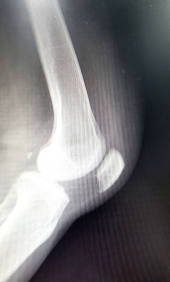

- 관절염 증상 완화: 관절염 환자들은 연골 조직의 파괴와 염증으로 고통을 겪습니다. 글루코사민은 이러한 증상을 완화시켜 관절의 유연성과 움직임을 증가시킬 수 있습니다.